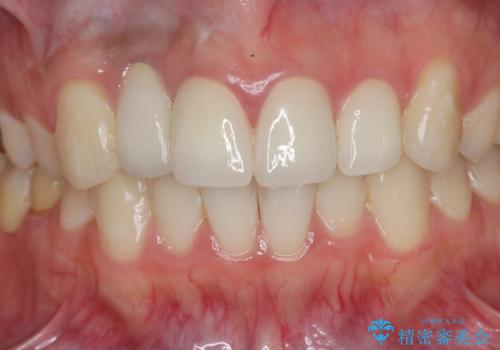

- 虫歯の治療を繰り返した前歯の見た目の改善を求めて来院されました。

大きく詰められたコンポジットレジンと虫歯の再発が見られ、経年劣化により審美性も損なわれていました。

充填されたコンポジットレジン・再発した虫歯を神経に影響が出ないよう丁寧に除去し再充填をしたのちオールセラミッククラウンで前歯の審美性を回復します。

- 33万円(仮歯・ジルコニアクラウン×3)費用は治療当時の料金となります